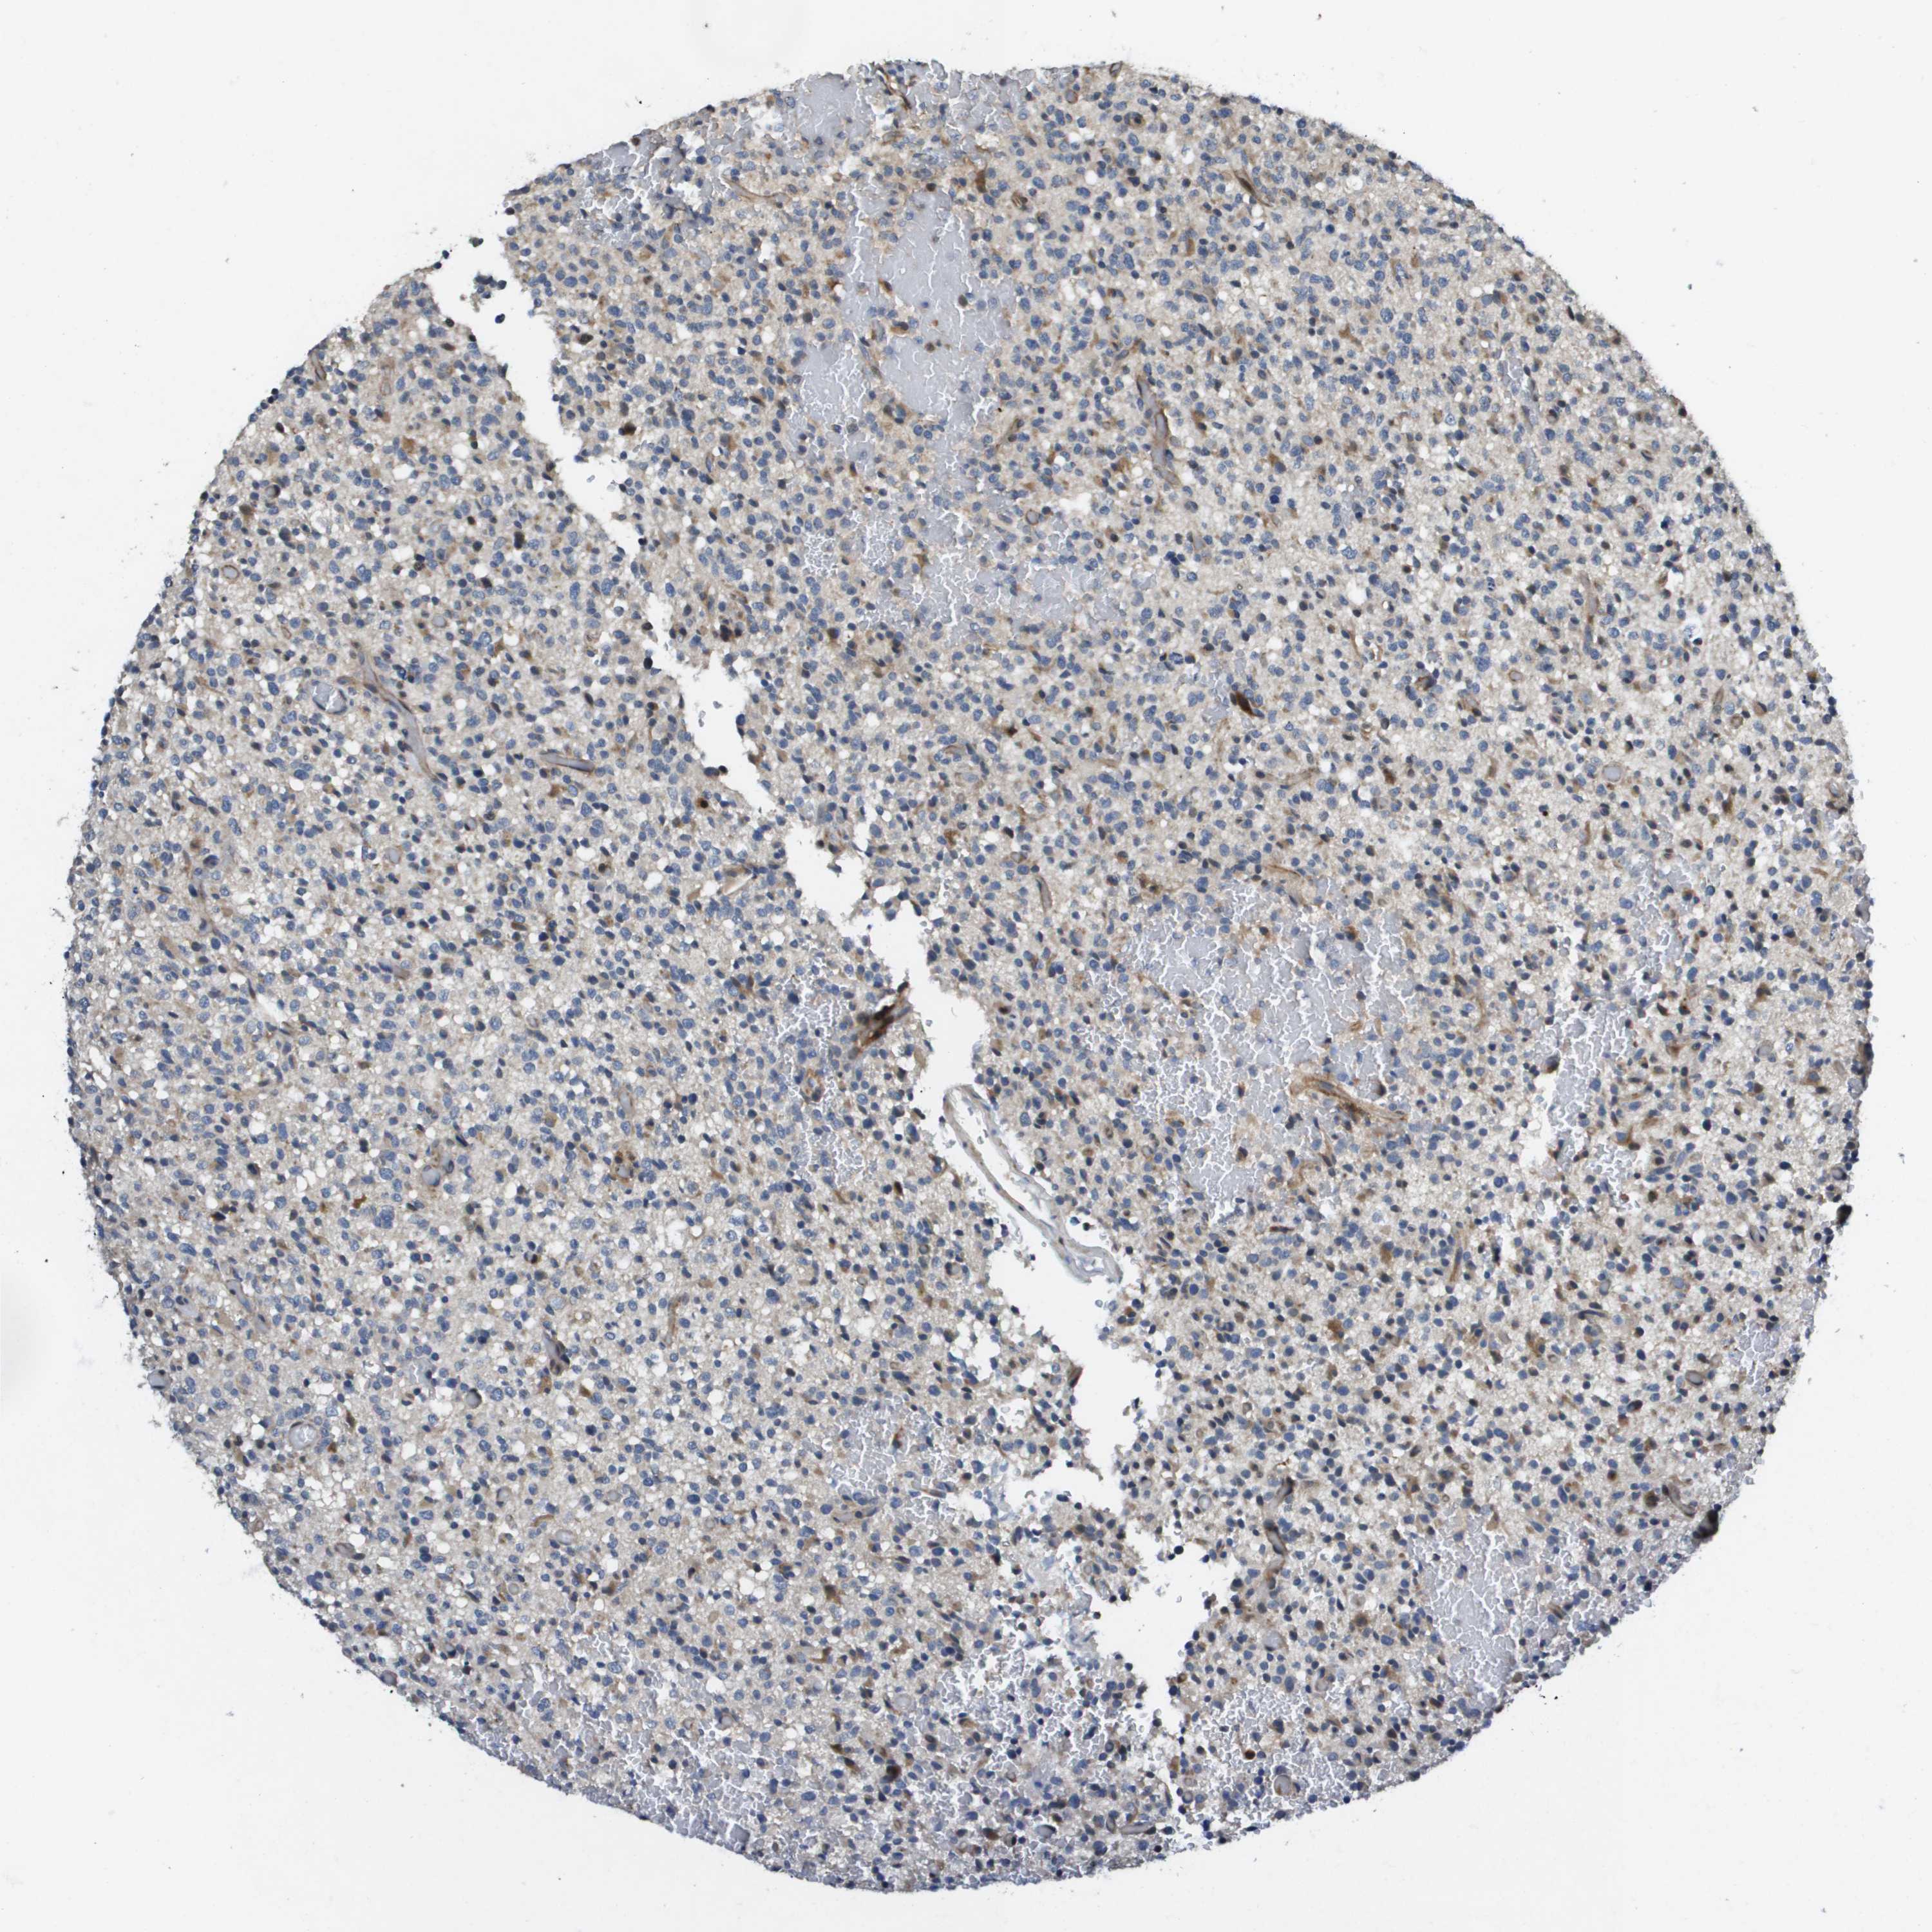

GLIOMA - Protein expressioni

A mouse-over function shows sample information and annotation data. Click on an image to view it in a full screen mode. Samples can be filtered based on level of antibody staining by selecting one or several of the following categories: high, medium, low and not detected. The assay and annotation is described here.

Note that samples used for immunohistochemistry by the Human Protein Atlas do not correspond to samples in the TCGA dataset.

Antibody stainingi

Antibody staining in the annotated cell types in the current human tissue is reported as not detected, low, medium, or high, based on conventional immunohistochemistry profiling in selected tissues. This score is based on the combination of the staining intensity and fraction of stained cells.

Each image is clickable and will lead to virtual microscopy that enables deeper exploration of all samples and also displays staining intensity scores, fraction scores and subcellular localization as well as patient and tissue information for each sample.

Antibody HPA017293

Staining

High

Medium

Low

Not detected

Intensity

Strong

Moderate

Weak

Negative

Quantity

>75%

75%-25%

<25%

None

Location

Nuclear

Cytoplasmic/membranous

Cytoplasmic/membranous,nuclear

Glioma, malignant, High grade

Glioma, malignant, Low grade